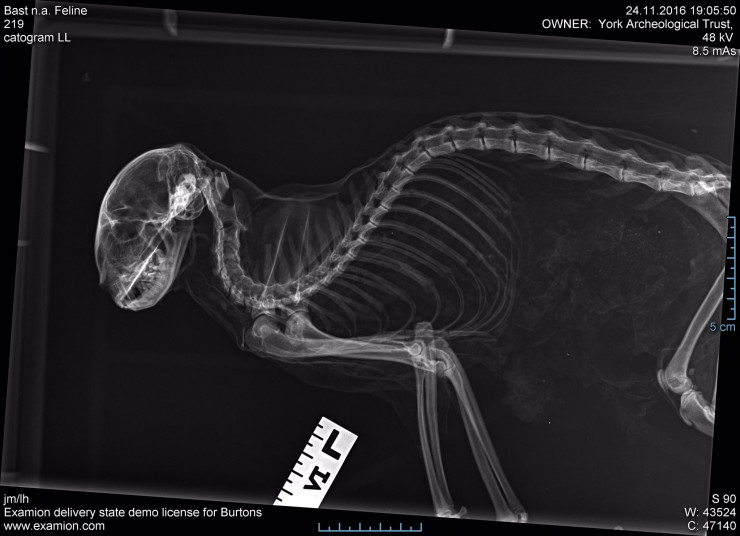

#18 "Мумифицированная кошка"

"История находки этой мумифицированной кошки куда страшнее, чем она сама. Ее обнаружили под половыми досками над нашим правительственным залом, окруженную кольцом из ореховых скорлупок", - сообщил аккаунт музея-особняка York Mansion House.